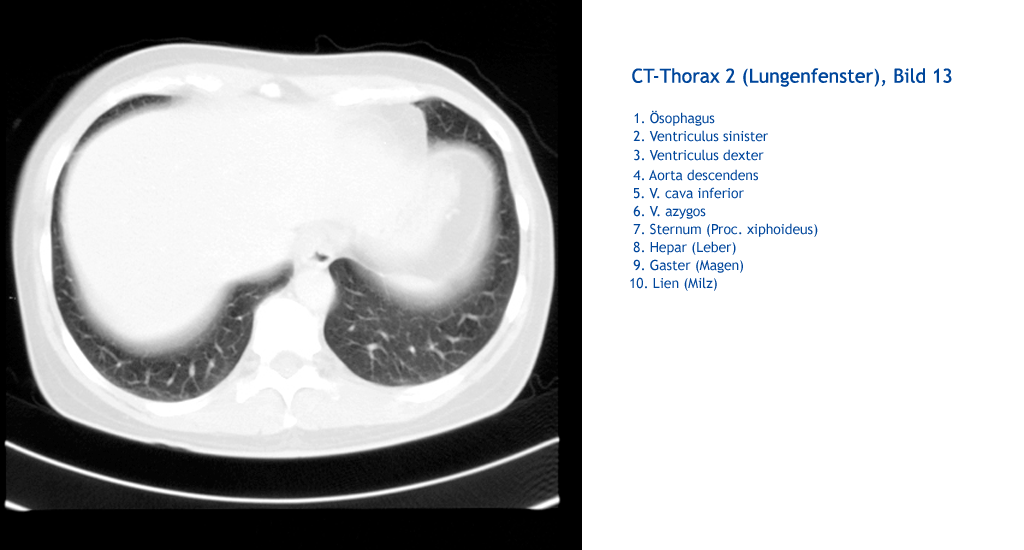

Lien (Milz) Gaster (Magen) Hepar (Leber) Sternum (Proc. xiphoideus) V. azygos V. cava inferior Aorta descendens Ventriculus dexter Ventriculus sinister Ösophagus